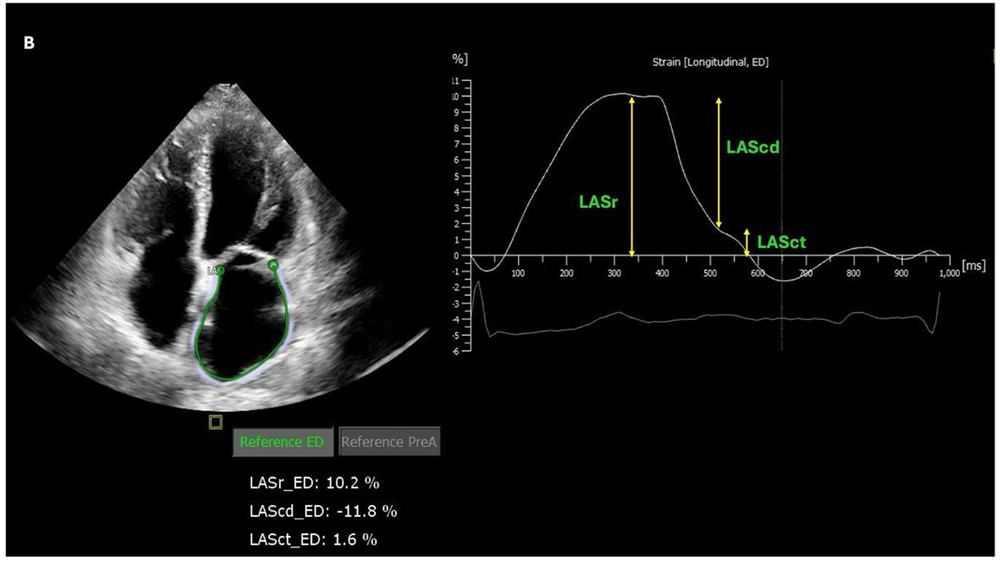

Só para recordarmos, a função atrial esquerda é classicamente dividida em 03 diferentes fases:

- Reservatório (LASr): durante a sístole ventricular, o AE funciona como reservatório do fluxo proveniente das veias pulmonares e esta função reflete a complacência desta cavidade, bem como a capacidade para acomodar o retorno venoso pulmonar;

- Conduto (LAScd): na diástole do ventrículo esquerdo (VE), o AE passa a funcionar como um conduto facilitando o esvaziamento passivo do fluxo das veias pulmonares para o VE;

- Bomba (LASct): já na fase de diástole final, ocorre finalmente a contração atrial, um processo ativo, que exerce papel funcional importante contribuindo por cerca de 20-30% do volume diastólico final do VE;

Assim sendo, a análise do strain do AE, através das fases de reservatório, conduto e bomba, fornece informações detalhadas sobre a complacência, contratilidade e função de forma geral desta cavidade.